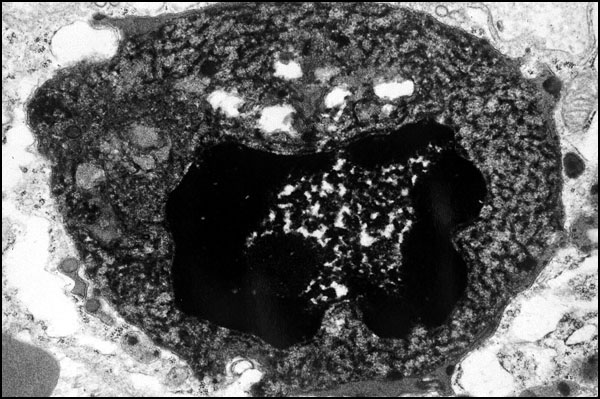

Necrosis of the liver induced by herpesvirus. Herpesvirus invades liver cell nuclei producing nuclear ("ground glass") mildly basophilic inclusions. Infected cells die and show typical nuclear changes such as karyolysis, karyorrhexis and pyknosis. Cells undergoing karyolysis show only vague nuclear contours. Karyorrhexis results in fragmentation of the nucleus ("nuclear dust"). Pyknotic nuclei appear as dense round globules reminiscent of the nuclei of lymphocytes.